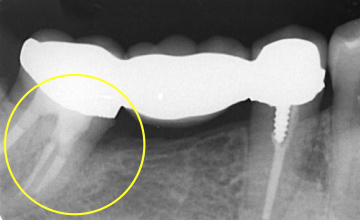

術前

術後

[治療内容] 右下7:歯周組織再生療法 [主訴] 右下の歯ぐきが痛い [目的] 歯周病で喪失した歯周組織の再生 [副作用・リスク] 術後疼痛、知覚過敏

歯肉退縮[治療期間(回数)] 約半年(手術は1回) [費用(税抜)] ¥75,000